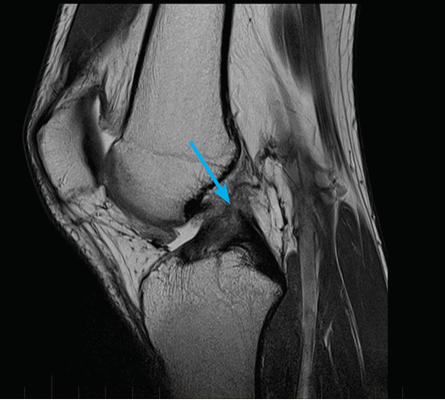

На снимке – разрыв крестообразной связки и мениска вследствие травмы колена

Для диагностики важна еще и форма мениска. В норме он в определенной плоскости имеет форму бабочки. Любые отклонения могут указывать на возможный разрыв.

Повреждение мениска нередко обнаруживается на МРТ на этапе отсутствия у человека существенных жалоб, такие случаи нередки у возрастных пациентов.